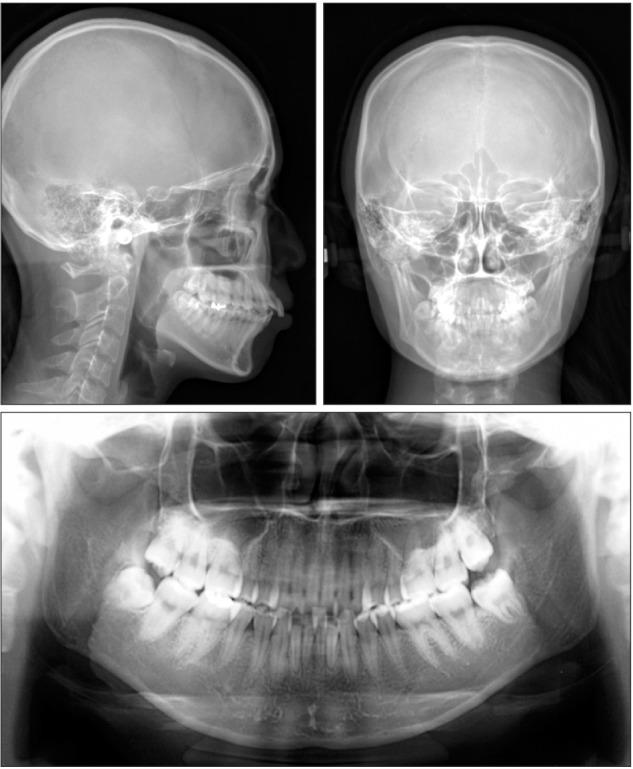

For patients with bimaxillary protrusion, significant retraction and intrusion of the anterior teeth are sometimes essential to improve the facial profile. However, severe root resorption of the maxillary incisors occasionally occurs after treatment because of various factors. For instance, it has been reported that approximation or invasion of the incisive canal by the anterior tooth roots during retraction may cause apical root damage. Thus, determination of the position of the maxillary incisors is key for orthodontic diagnosis and treatment planning in such cases. Cone-beam computed tomography (CBCT) may be useful for simulating the post-treatment position of the maxillary incisors and surrounding structures in order to ensure safe teeth movement. Here, we present a case of Class II malocclusion with bimaxillary protrusion, wherein apical root damage due to treatment was minimized by pretreatment evaluation of the anatomical structures and simulation of the maxillary central incisor movement using CBCT. Considerable retraction and intrusion of the maxillary incisors, which resulted in a significant improvement in the facial profile and smile, were achieved without severe root resorption. Our findings suggest that CBCT-based diagnosis and treatment simulation may facilitate safe and dynamic orthodontic tooth movement, particularly in patients requiring maximum anterior tooth retraction.

对于双颌前突患者,有时显著内收和压低前牙对于改善面部外形至关重要。然而,由于多种因素,治疗后上颌切牙偶尔会出现严重的牙根吸收。例如,有报道称,内收过程中前牙根尖接近或侵入切牙管可能会导致根尖牙根损伤。因此,确定上颌切牙的位置是此类病例正畸诊断和治疗计划的关键。锥形束计算机断层扫描(CBCT)可能有助于模拟上颌切牙及周围结构的治疗后位置,以确保牙齿安全移动。在此,我们展示一例双颌前突的安氏II类错牙合病例,其中通过对解剖结构的预处理评估和使用CBCT模拟上颌中切牙移动,将治疗引起的根尖牙根损伤降至最低。在没有严重牙根吸收的情况下,实现了上颌切牙的大量内收和压低,从而显著改善了面部外形和笑容。我们的研究结果表明,基于CBCT的诊断和治疗模拟可能有助于实现安全、动态的正畸牙齿移动,特别是在需要最大程度内收前牙的患者中。